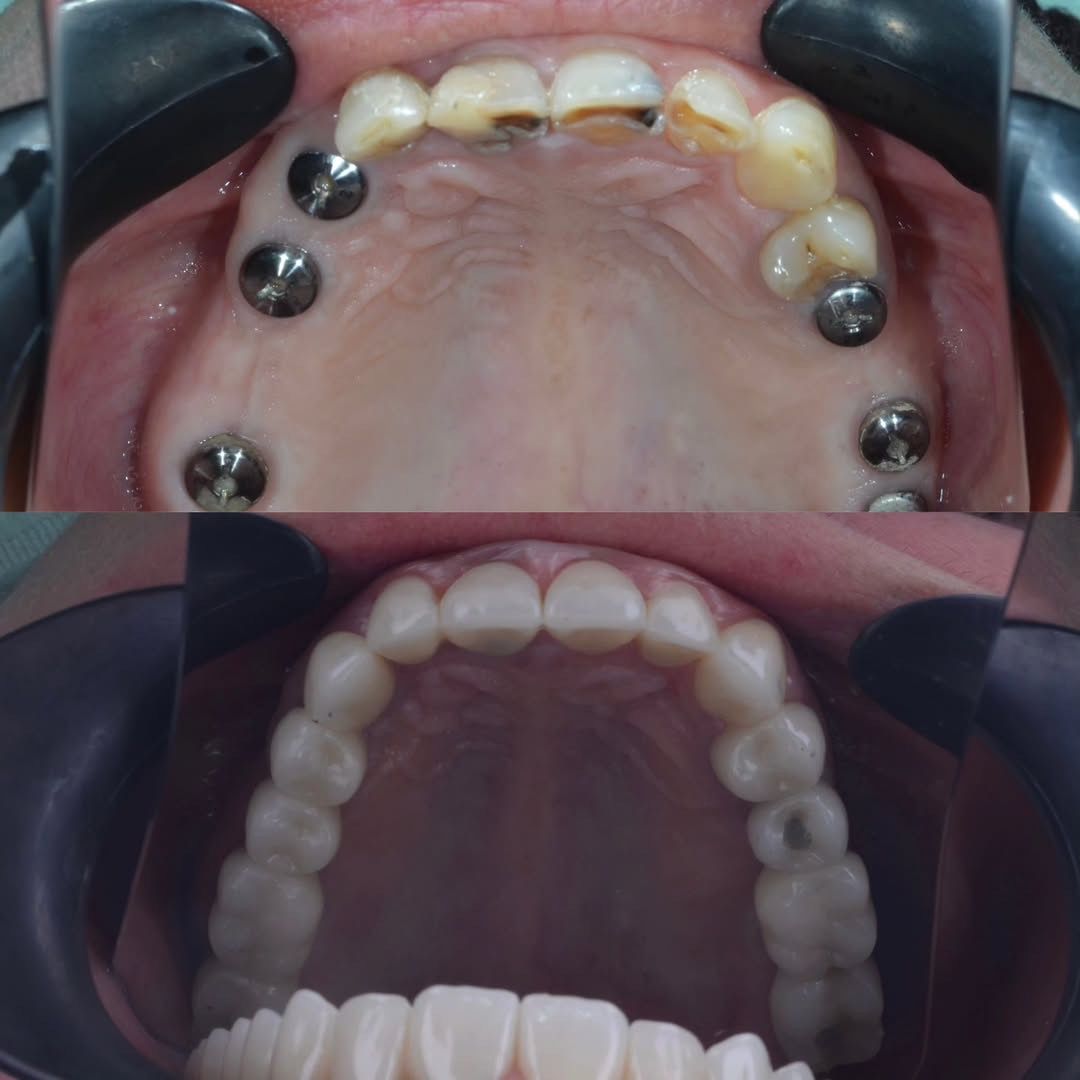

Имплантация зубов челюсти - фото до и после

Имплантация зуба

Протезирование